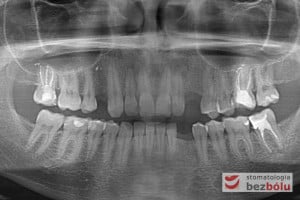

Po zakończeniu procesu gojenia wyrostka zębodołowego, wykonano diagnostykę radiologiczną z zastosowaniem tomografii wiązki stożkowej (CBCT) w celu oceny ilości oraz jakości tkanki kostnej, zarówno w miejscach poekstrakcyjnych, jaki i w pozycji górnego prawego przedtrzonowca. Ponadto pobrano wyciski, oddające sytuację kliniczną w jamie ustnej pacjenta, który zdecydował się na metodę implantacyjną, wykorzystującą nawigację komputerową, z zastosowaniem protokołu MGuide firmy MIS. Procedura ta polega na cyfrowym zaplanowaniu pozycji implantów, a następnie wykonaniu w technice druku 3D szablonu chirurgicznego.Taka metoda pozwala wyeliminować konieczność odwarstwiania płatów, zmniejszając przy tym pozabiegowe dolegliwości. Usprawnia jednocześnie pracę operatora, dokładnie pozycjonując wszczep w pożądanej pozycji. Kolejnym krokiem było przesłanie skanów modeli gipsowych oraz tomografii do siedziby MCenter w Berlinie, gdzie wysoko wyspecjalizowani technicy, dysponujący najnowszą technologią cyfrową, precyzyjnie wykonali szablony nawigacyjne, stosowane podczas zabiegu implantologicznego.

Procedurę chirurgiczną rozpoczęto od sprawdzenia przylegania szablonów do zębów pacjenta oraz znieczulenia miejscowego. W kolejnym kroku, przy pomocy specjalnie przeznaczonego do tego celu zestawu wierteł, wypreparowano krążki dziąsła punktowo odsłaniające kość a następnie poprzez tuleje prowadzące, z najwyższą precyzją, opracowano łoże implantu. Kulminacyjny moment zabiegu, czyli wprowadzenie wszczepów MIS C1 również odbyło się poprzez szablon, gwarantując precyzyjną lokalizację implantów. Zwieńczeniem całej procedury było przyszycie uprzednio wypreparowanych krążków śluzówkowo-okostnowych. Tuż po zabiegu, celem weryfikacji poprawnej pozycji implantów, wykonano zdjęcie ortopantomograficzne. Podczas wizyt kontrolnych, pacjent nie skarżył się na żadne dolegliwości bólowe, nie wystąpił obrzęk, a zreponowane we właściwych miejscach fragmenty dziąsła nie wykazywały oznak martwicy, co świadczyło o ich ponownym ukrwieniu i wgojeniu się. Wszystkie te przesłanki jasno wskazują na skuteczność zastosowania techniki komputerowej nawigacji w implantologii.